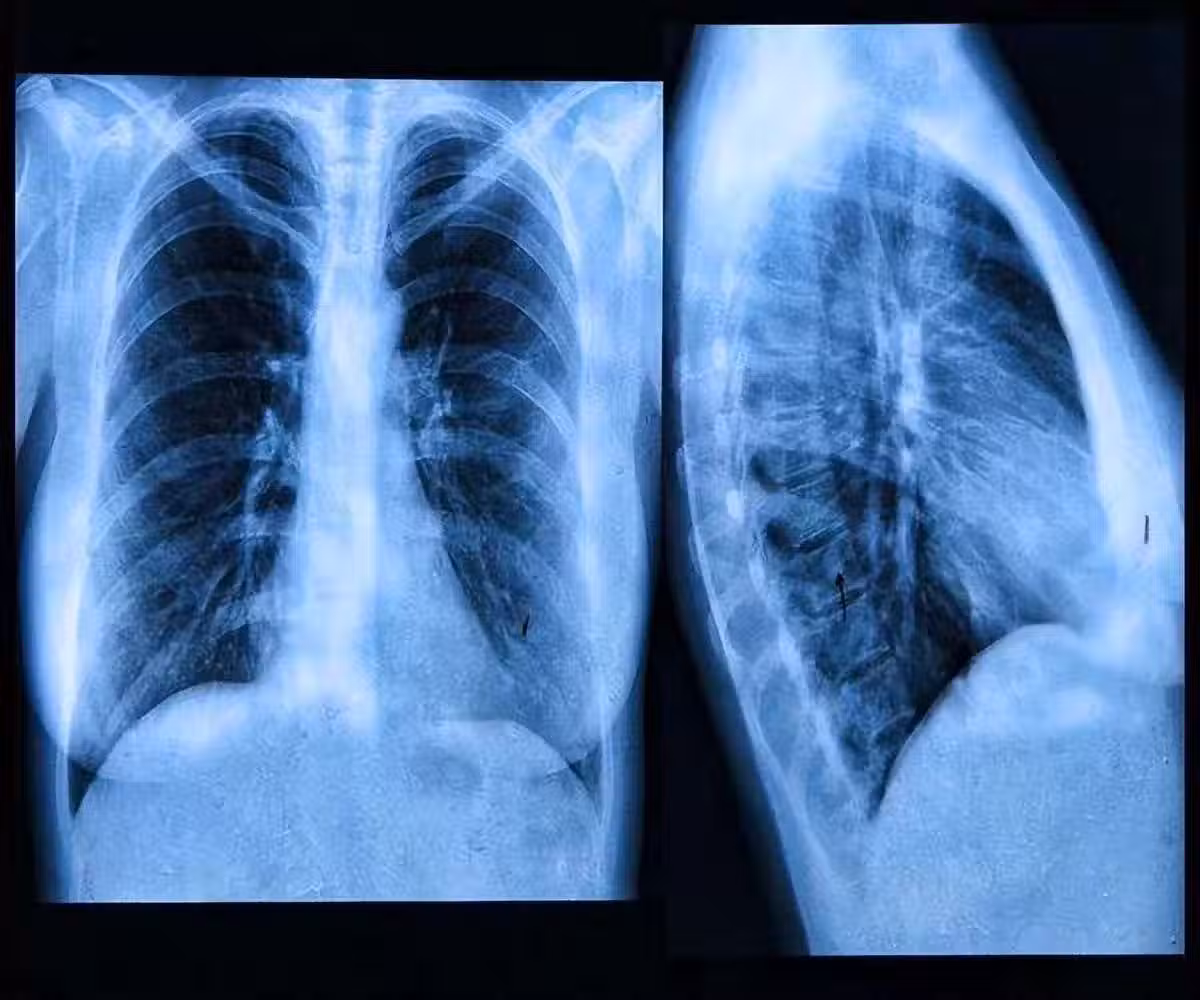

肺內有癌,腿疼告知?事實上,早期肺癌的5個跡象你更需要去留意!

4、肺部持續疼痛

如果人的肺部持續疼痛,也有可能是肺癌造成的,隨著病情的發展,肺癌也會引起骨骼疼痛和肌肉疼痛。

這種痛感多發生在背部和肩部,運動程度越大,疼痛感也會有所增加。因此患上肺癌是禁止做任何劇烈運動的。